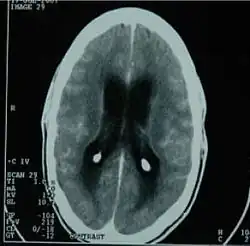

| CT scan showing tuberculous meningitis | |